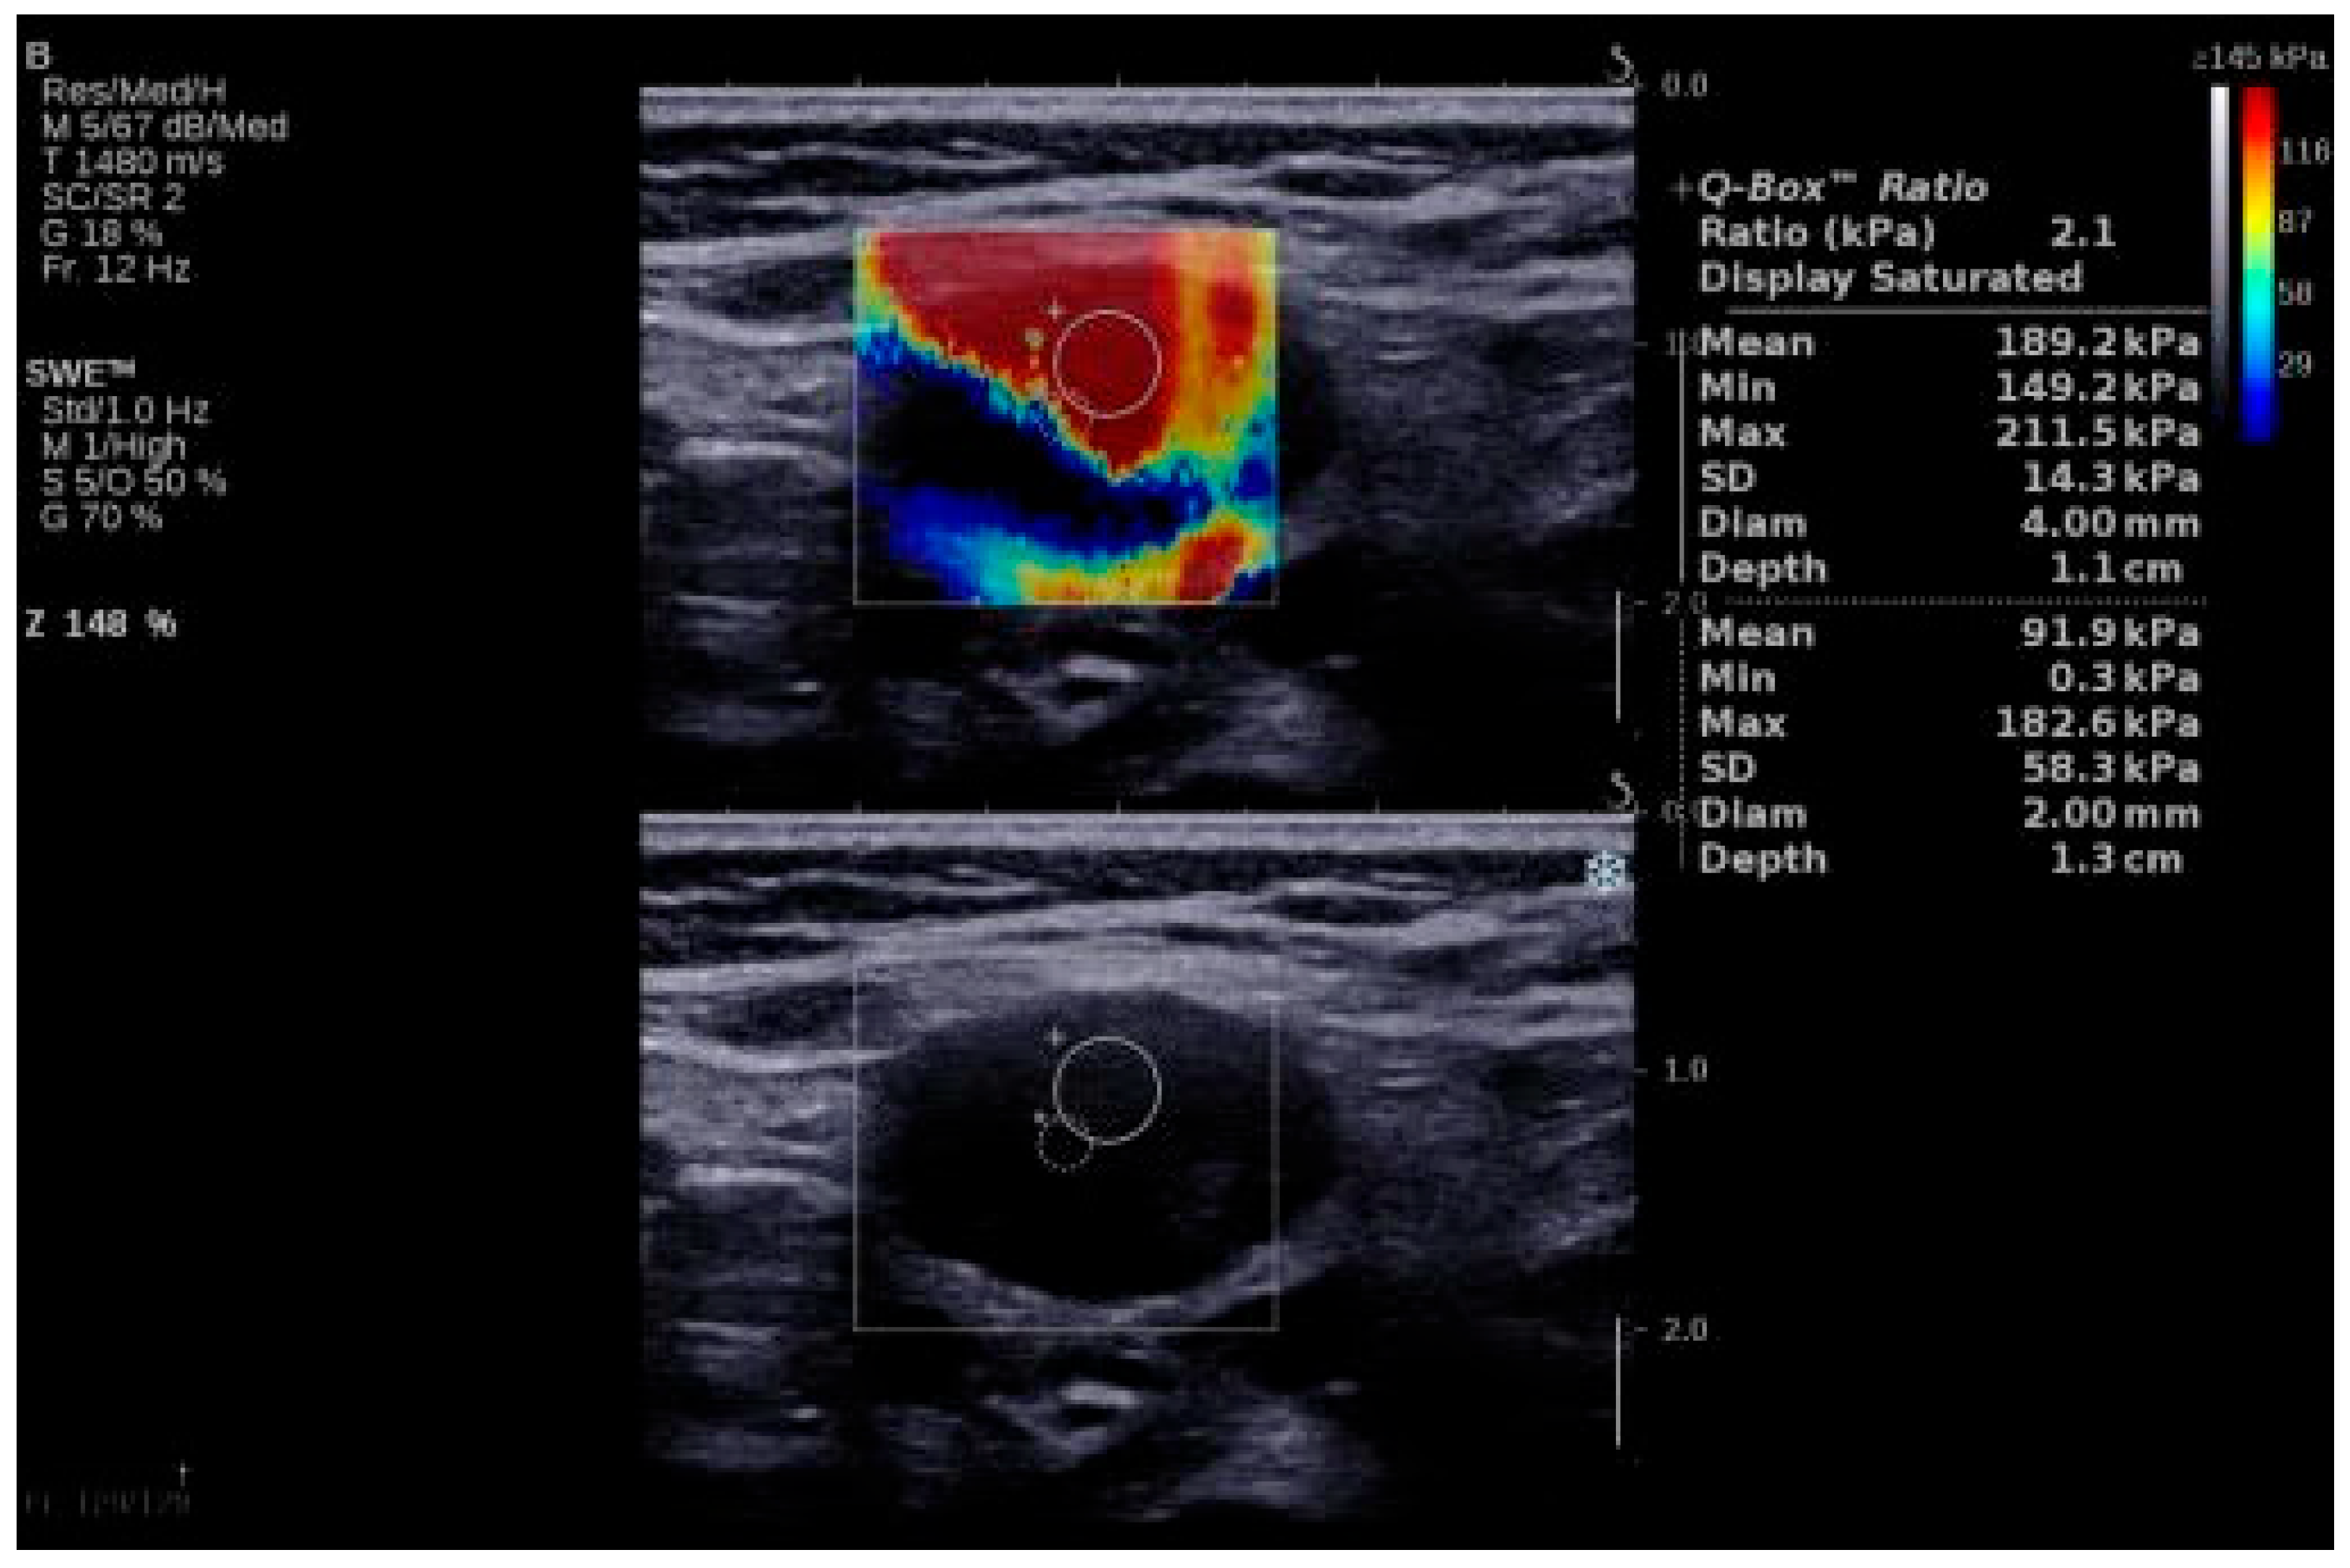

Examples of SWE analyses of malignant lymph nodes are provided in Figure 1 and Figure 2, and descriptive statistics of SWE by histopathology type (participants with benign cervical lymph nodes, participants with lymphoma and cervical lymphadenopathy, and participants with cervical lymph node metastasis of solid tumors) are shown in Table 3. The maximum SWE value for patients with benign pathologies was 35 kPa, which is lower than both minimal values for lymphoma (40 kPa) and metastases (50 kPa). These results suggest that SWE values under 40 kPa are associated with benign cervical lymph nodes. Given the differences between the benign and malignant lymph nodes highlighted by the SWV, we further concentrated our attention on the differences in tissue stiffness that can be seen in the malignant group and the capacity of SWE in differentiating between the metastatic and lymphoma lymph nodes.

Figure 1.

SWE of an LN in a 55-year-old patient with diffuse large B-cell lymphoma. LN, lymph node; SWE, shear wave elastography.